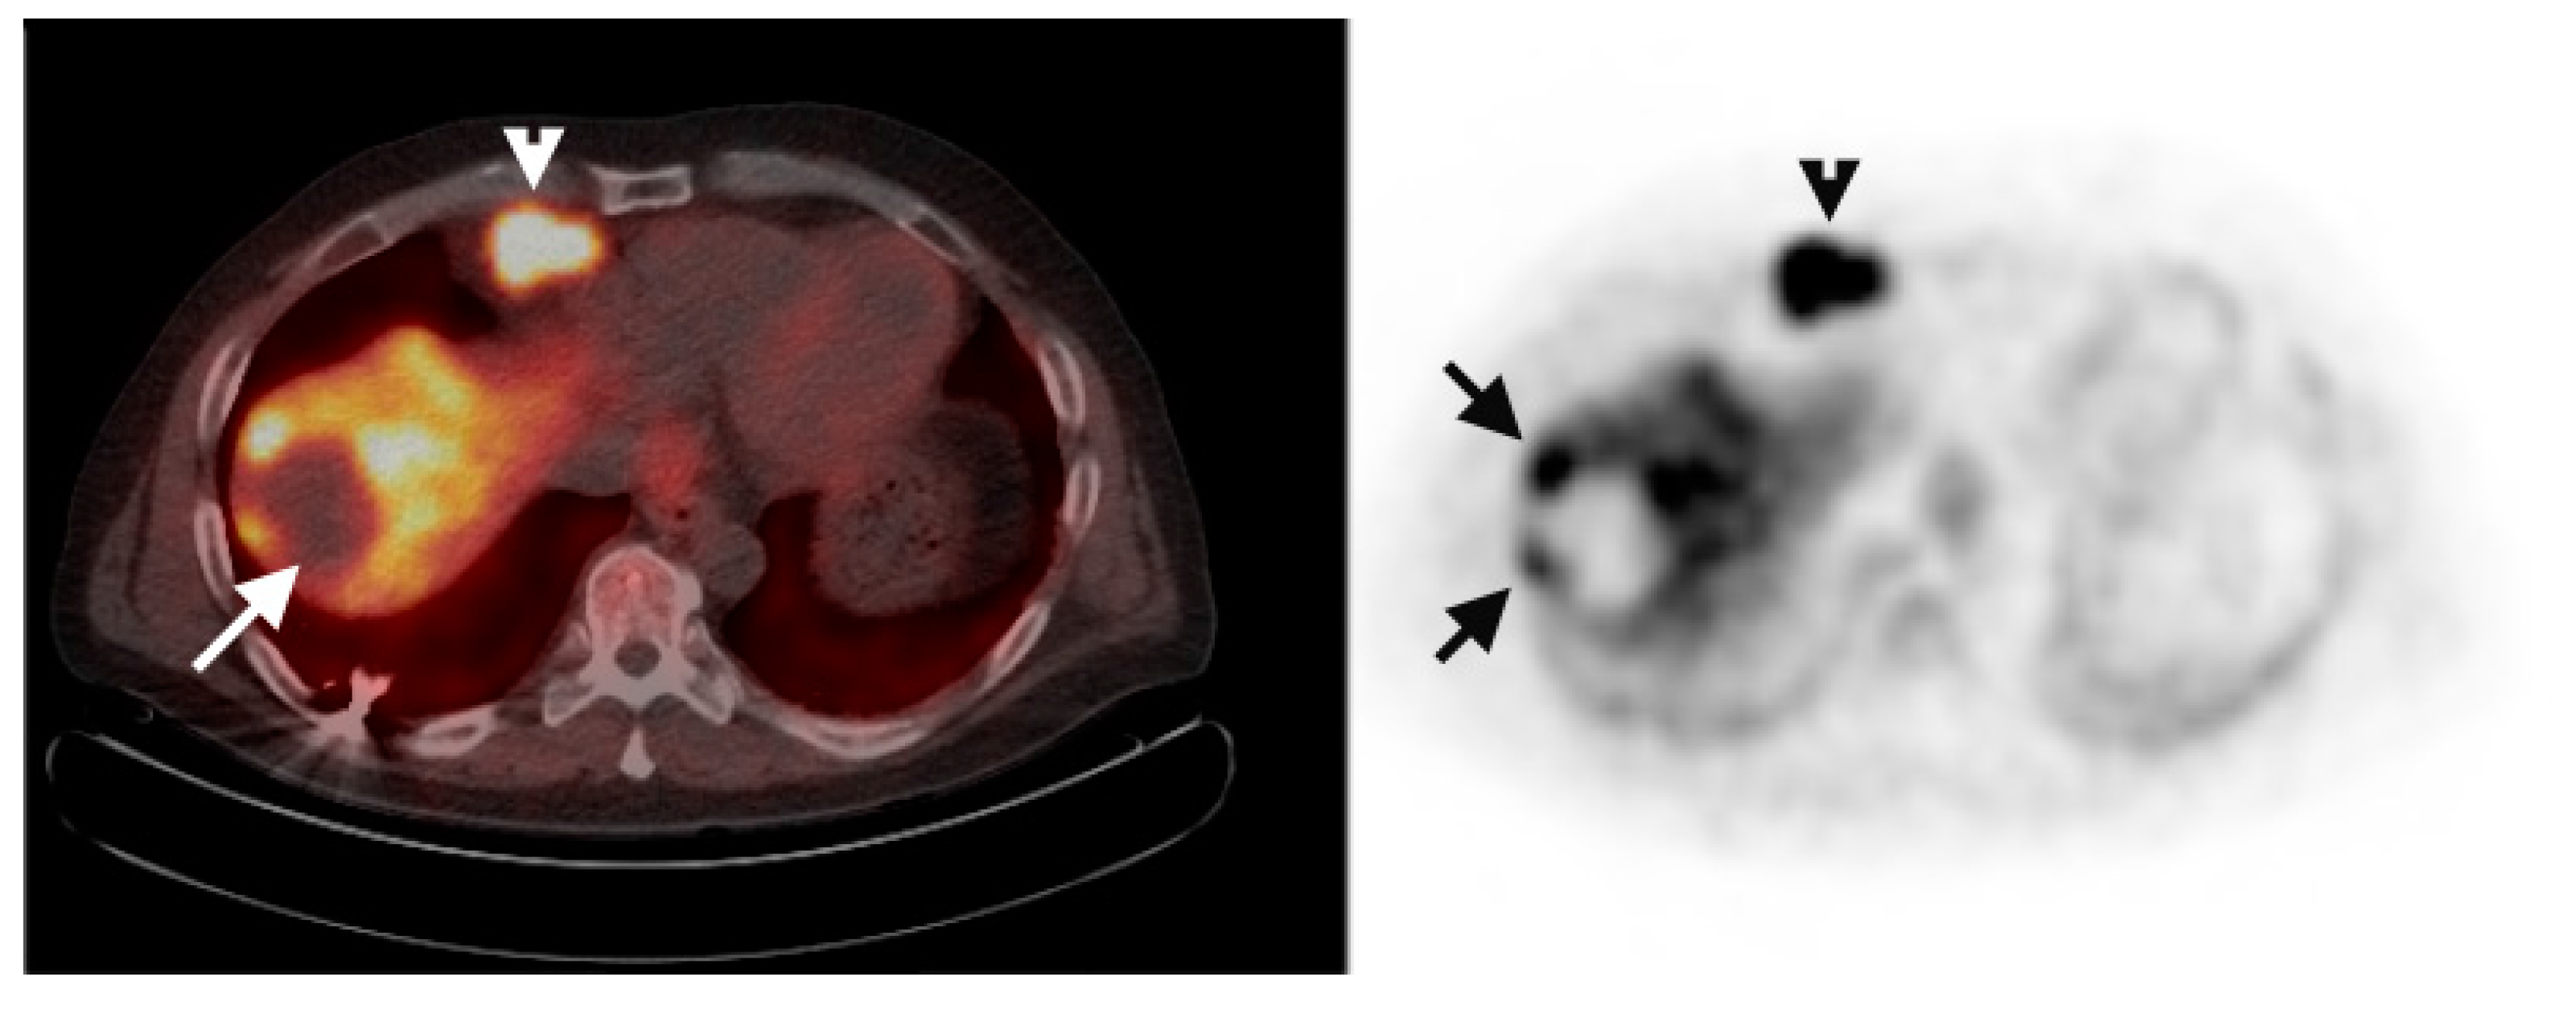

Multiple foci of increased FCh uptake in the liver consistent with multifocal or multinodular HCC (example, Figure 1) were noted in 8 of the 13 patients with increased primary tumor uptake. Of these, the areas of increased FCh uptake were adjacent to the treatment site (examples, Figure 2 and Figure 3) in 2 patients treated by local tumor ablation and 1 patient treated by liver resection. In one newly diagnosed case, PET demonstrated heterogeneous tumor FCh uptake with increased peripheral uptake and markedly diminished central uptake (Figure 4). Pathology in this case revealed a highly-necrotic tumor with Edmondson-Steiner grade 3 differentiation.

Figure 4.

Metabolic heterogeneity in HCC. Corresponding PET/CT (left) and PET (right) shows a heterogeneous region of increased uptake within the liver in this patient with newly diagnosed liver mass. Two small satellite tumors (arrows) are adjacent to the dominant mass (arrowheads surround). Histologically, this was a poorly differentiated HCC tumor.